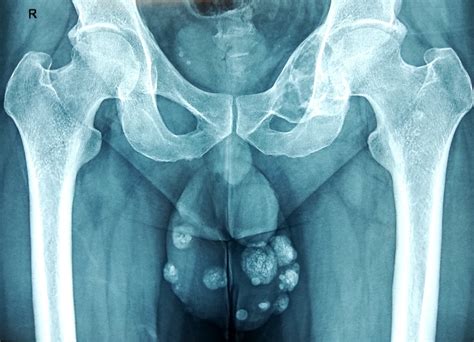

A cyst on scrotum is essentially a closed sac or capsule filled with fluid, semi-solid material, or keratin (a protein found in skin). These structures can appear anywhere on the body, but when they form within or on the skin of the scrotum, they are often referred to as epidermoid or sebaceous cysts. They generally feel like small, firm, and sometimes movable lumps beneath the surface of the skin.

These cysts are typically slow-growing and painless unless they become irritated, inflamed, or infected. It is important to distinguish them from other types of scrotal masses, such as hydroceles (fluid buildup around the testicle), varicoceles (enlarged veins), or testicular tumors, which require entirely different approaches to diagnosis and treatment.

Testicular Tumor Hard mass on the testicle Usually firm/hard, painless, requires immediate checkup.